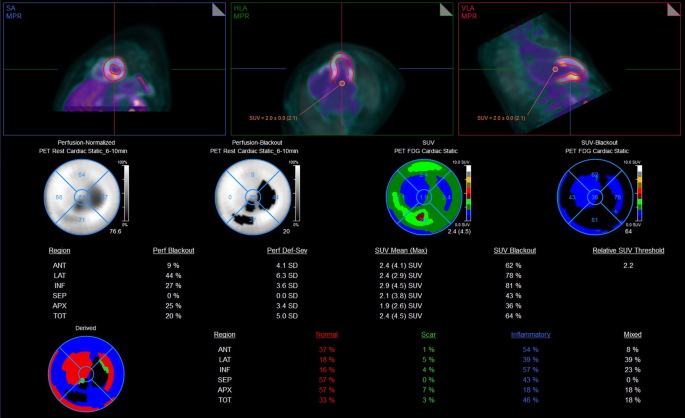

Increased metabolic activity/hypermetabolism was characterized by 2-[18F]FDG uptake with normal [13N]-NH3 PET perfusion; fibrotic myocardium was characterized by no 2-[18F]FDG uptake with reduced [13N]-NH3 PET perfusion. Hypermetabolism and fibrosis/scar extension were expressed globally as a percentage of LV involvement and regionally (apex, septum, anterior, inferior, and lateral walls) (Fig. 1). Maximum Target to Background Ratio (TBR) of the LV and of each of its walls was also evaluated by the same software.

Final Software Processing of 2-[18F]FDG Myocardial uptake analysis. Top panel: short-axis, horizontal long-axis and vertical long-axis images from 2-[18F]FDG PET/CT with LV volume of interest (VOI) superimposed as defined in the perfusion PET. A VOI in the LV cavity was drawn to determine blood pool activity. The 2-[18F]FDG threshold was calculated as the blood pool activity (SUV mean) multiplied by a factor of 1.1. Middle panel: Left: Rest [13N]NH3 perfusion polar plots. The first plot shows average perfusion, percentage wise, per region. The blackout areas in the second plot indicate abnormally low perfusion. Right: 2-[18F]FDG uptake (metabolism) polar plots. The third plot indicates the average SUV for each region. The black areas in the fourth plot indicate abnormally high 2-[18F]FDG uptake (SUV exceeds the threshold). Bottom panel: Integration of the rest [13N]NH3 perfusion and 2-[18F]FDG myocardial uptake analysis identifies distinct patterns: Scar (green): Reduced perfusion and no significant 2-[18F]FDG uptake (referred to, in the text, as fibrosis). Inflammatory myocardium (blue): Normal perfusion and increased 2-[18F]FDG uptake (referred to, in the text, as hypermetabolic myocardium). These patterns are expressed as percentages of the total left ventricle and further categorized according to five regions: apex, septum, anterior wall, inferior wall, and lateral wall. In the example provided, the patient exhibited 33% normal myocardium, 46% inflammatory (hypermetabolic) myocardium and 3% scar (fibrosis) extension.